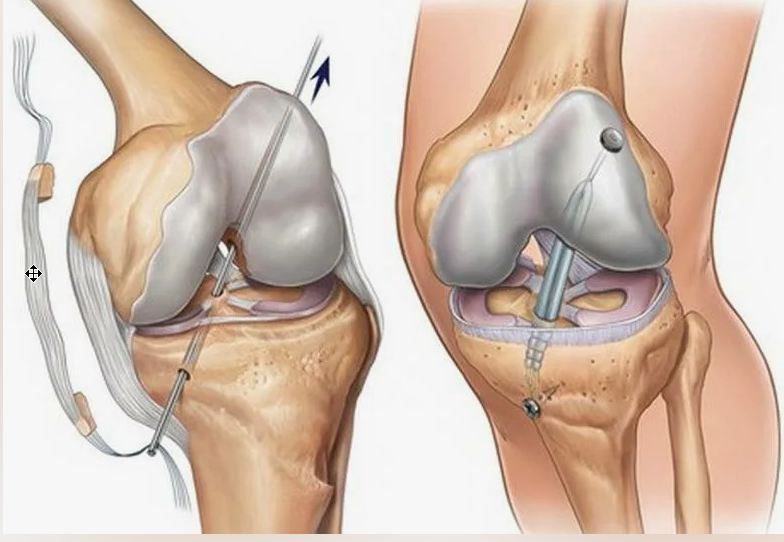

Анатомия коленного сустава: изучение анзерита и его влияния